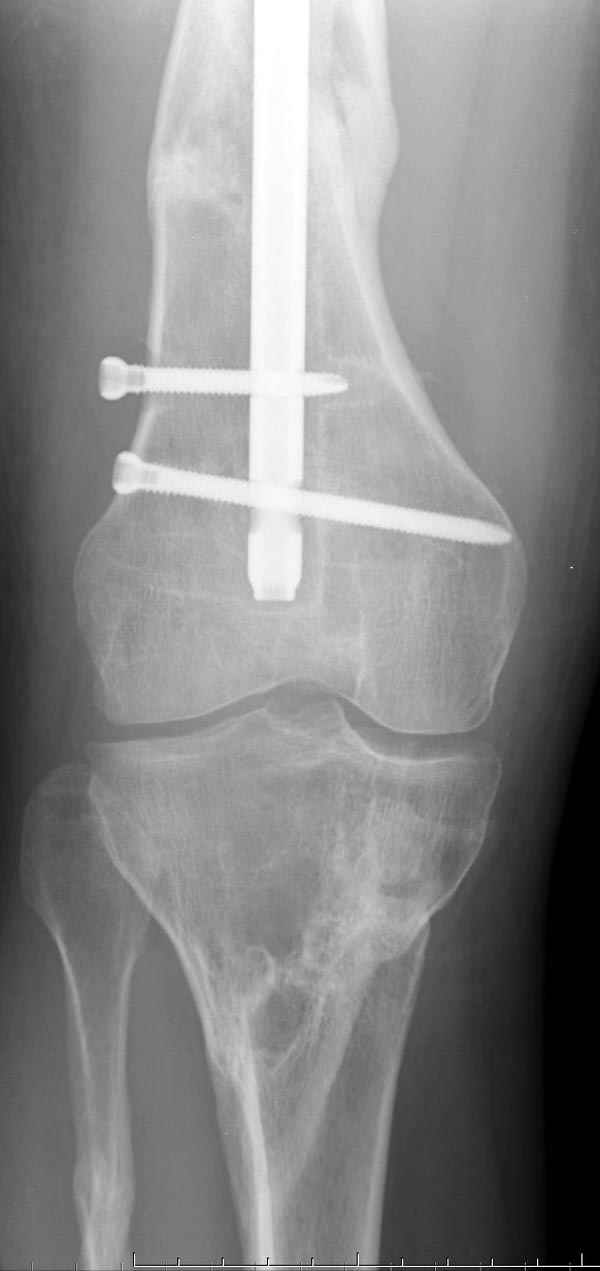

Рутинный интрамедуллярный остеосинтез с расверливанием и с фиксацией реконструктивным трокантерик штифтом (рис №1, №2),

если первые 4 месяца послеоперационного периода проходил без проблем, но на 5 месяце появились боли в дистальном отделе бедра и температура, т.е. симптомы медуллярного инфицирования (рис №3, №4).